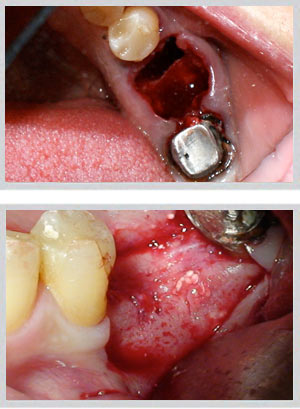

When upper back teeth are lost, the sinus floor descends and bone height decreases — often making standard implant placement unsafe without first elevating the sinus membrane and grafting the space below it.

• Internal sinus lift: For moderate bone loss (4–8mm available). Performed through the implant site itself, less invasive, with implant placement often possible in the same session.

• External lateral window sinus lift: For significant bone deficiency (less than 4mm). A lateral window allows direct access to the sinus membrane and larger graft volume. Implants are typically placed after a healing period.

Upper jaw: GBR (guided bone regeneration) for moderate buccal defects; block bone grafting for larger volume requirements. Socket preservation at time of extraction prevents bone loss from occurring in the first place.

Lower jaw: Block bone grafting for severe buccal wall defects. Easy Graft Crystal (non-resorbable beta-tricalcium phosphate) for minor to moderate deficiencies. Socket preservation equally critical.